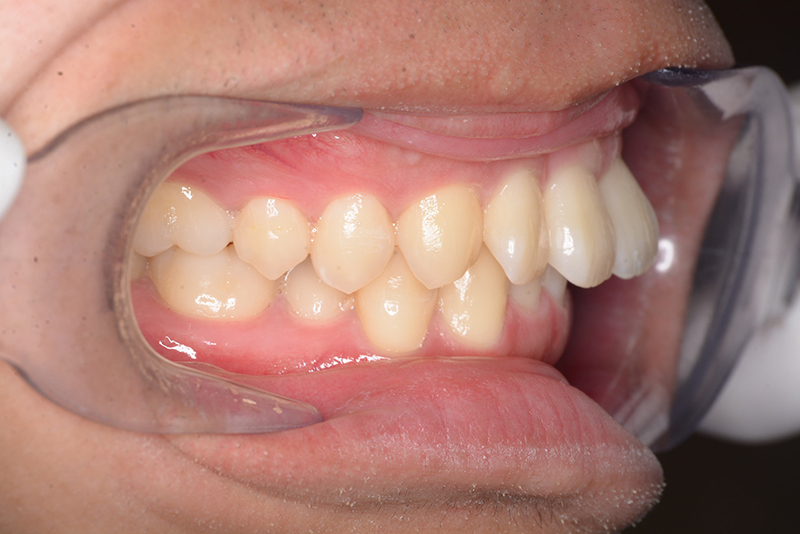

初診時

FP・IOP

主訴 物が噛みづらい 診断名 下顎右側側切歯先天欠如を伴う過蓋咬合症例

口腔内所見 over jet 8.5mm、over bite 6.0mm、下顎前歯先天欠如、右側臼歯関係I級、左側II級(end on)、上顎歯列弓はオーボイド型なのに対して、下顎は狭窄歯列、叢生歯列弓を呈しており左側は鋏状咬合となっていた。